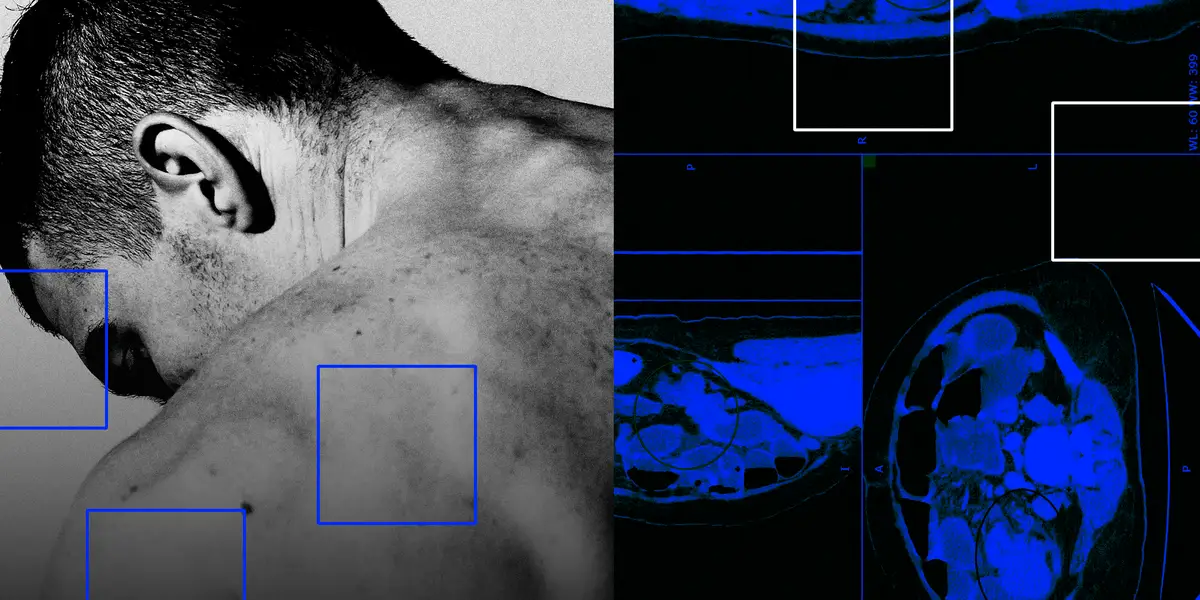

A 35-year-old father was diagnosed with late-stage colon cancer, underwent chemotherapy, then adopted a regimen of twice-weekly strength training plus cardio and a fiber-rich Mediterranean-style diet. He notes exercise may be as effective as drugs at preventing relapse and cites research, while advocating early screening and awareness for under-50s.